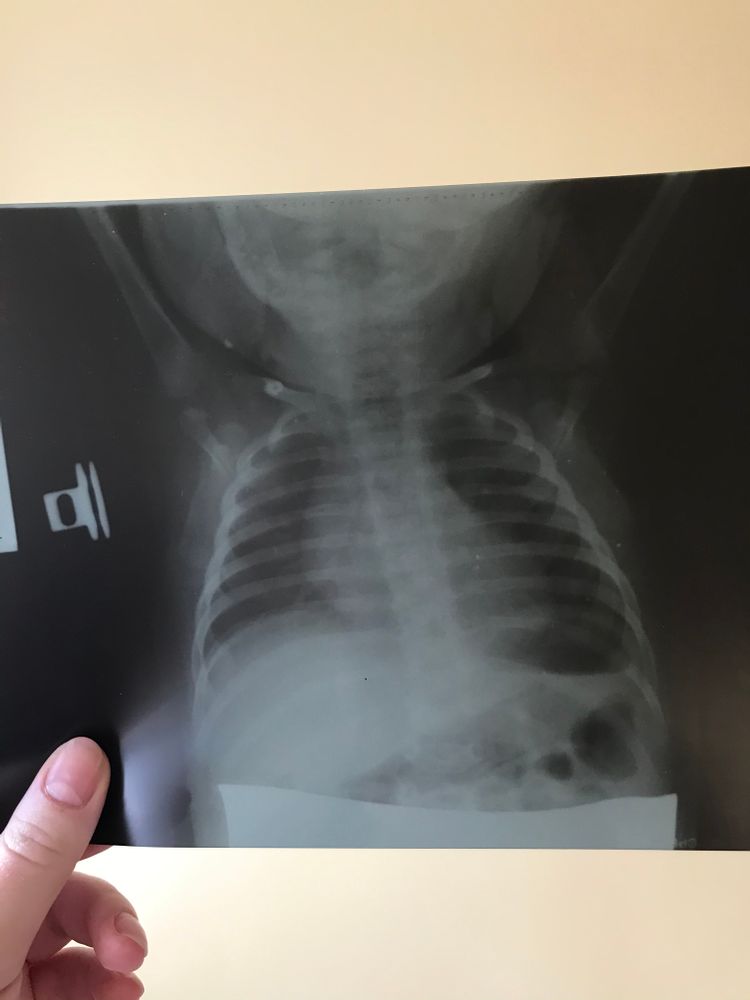

Мы тоже все переболели. Дочери полтора месяца было. Сначала сонливая пару дней была, но температуры небыло. А потом температура поднялась с 37 до 38,5 буквально за час. Мы уже приехали в больницу. Дочь серая стала в красную клетку. Рвала, пена шла со рта. Кричать уже не могла и глаза не открывала. Нас госпитализировали как просто с орв, а потом я узнала, что у свекрови ковид и рассказала об этом медсёстрам. Нам сделали тест и он оказался положительным. Вызвали скорую и перевезли нас в инфекционку в красную зону. Лечили антибиотиками, капали, куча препаратов перорально, узи, рентгены. Это было страшно. В соседней палате девочка, 10 месяцев, умерла. Но у неё был сопутствующий туберкулёз к ковиду. Желаю вам не терять самообладания. Крепитесь. Такой сложный период. Потом иммунитет будет, думайте о нем